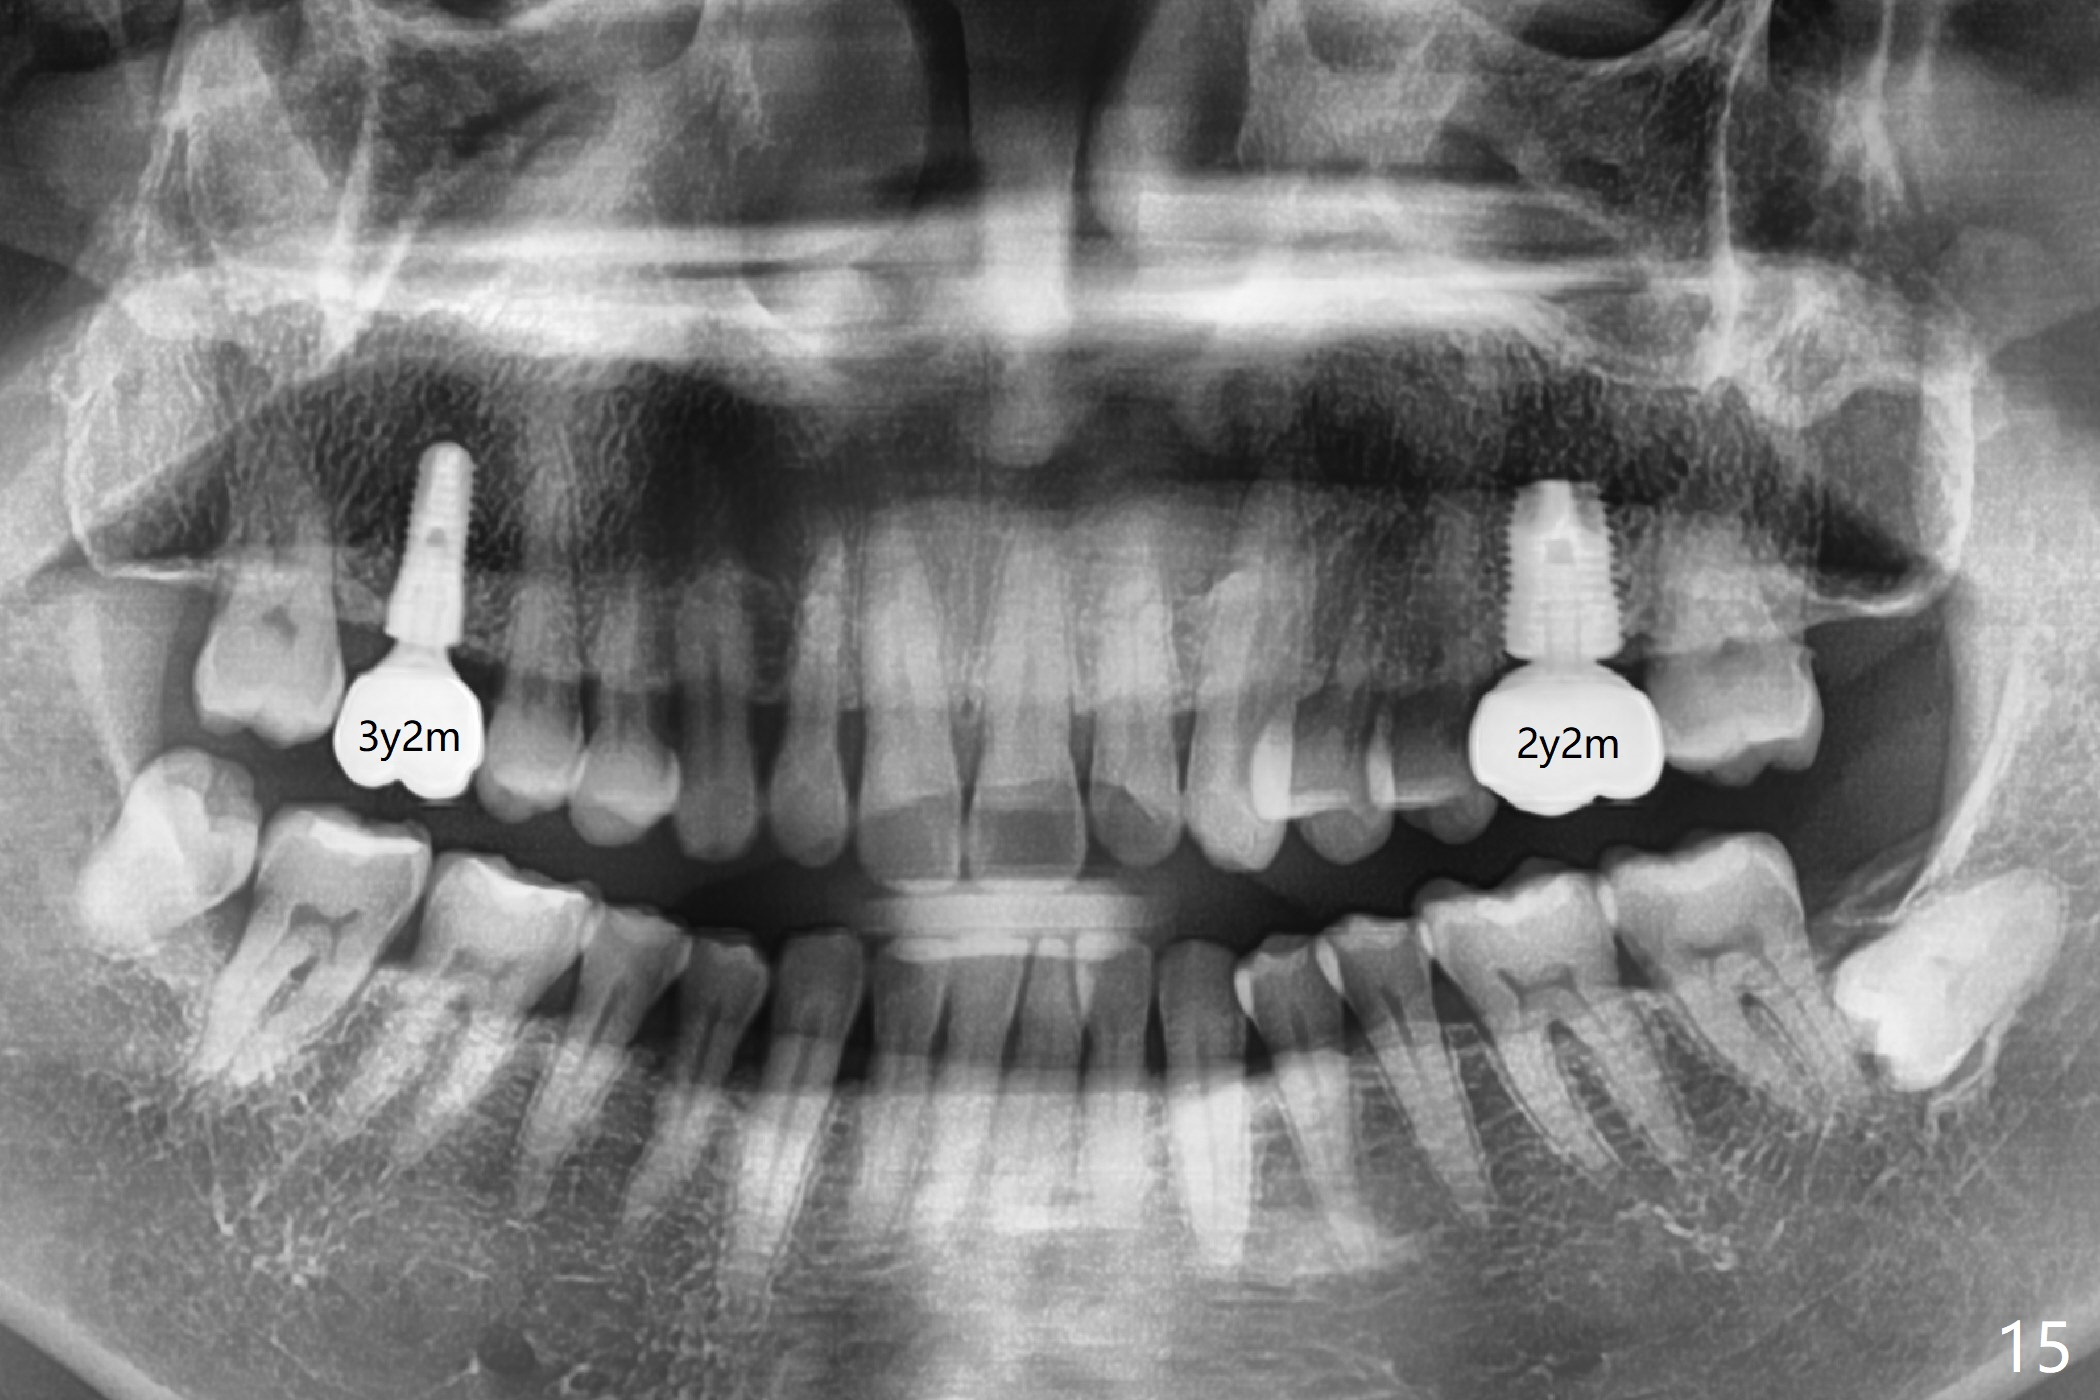

The crowns at #3 and 14 have been cemented for 3 years 2 months and 2 years 2 months, respectively (Fig.15).

Small Immediate Implant Placed in the Septum with Large Healing Abutment